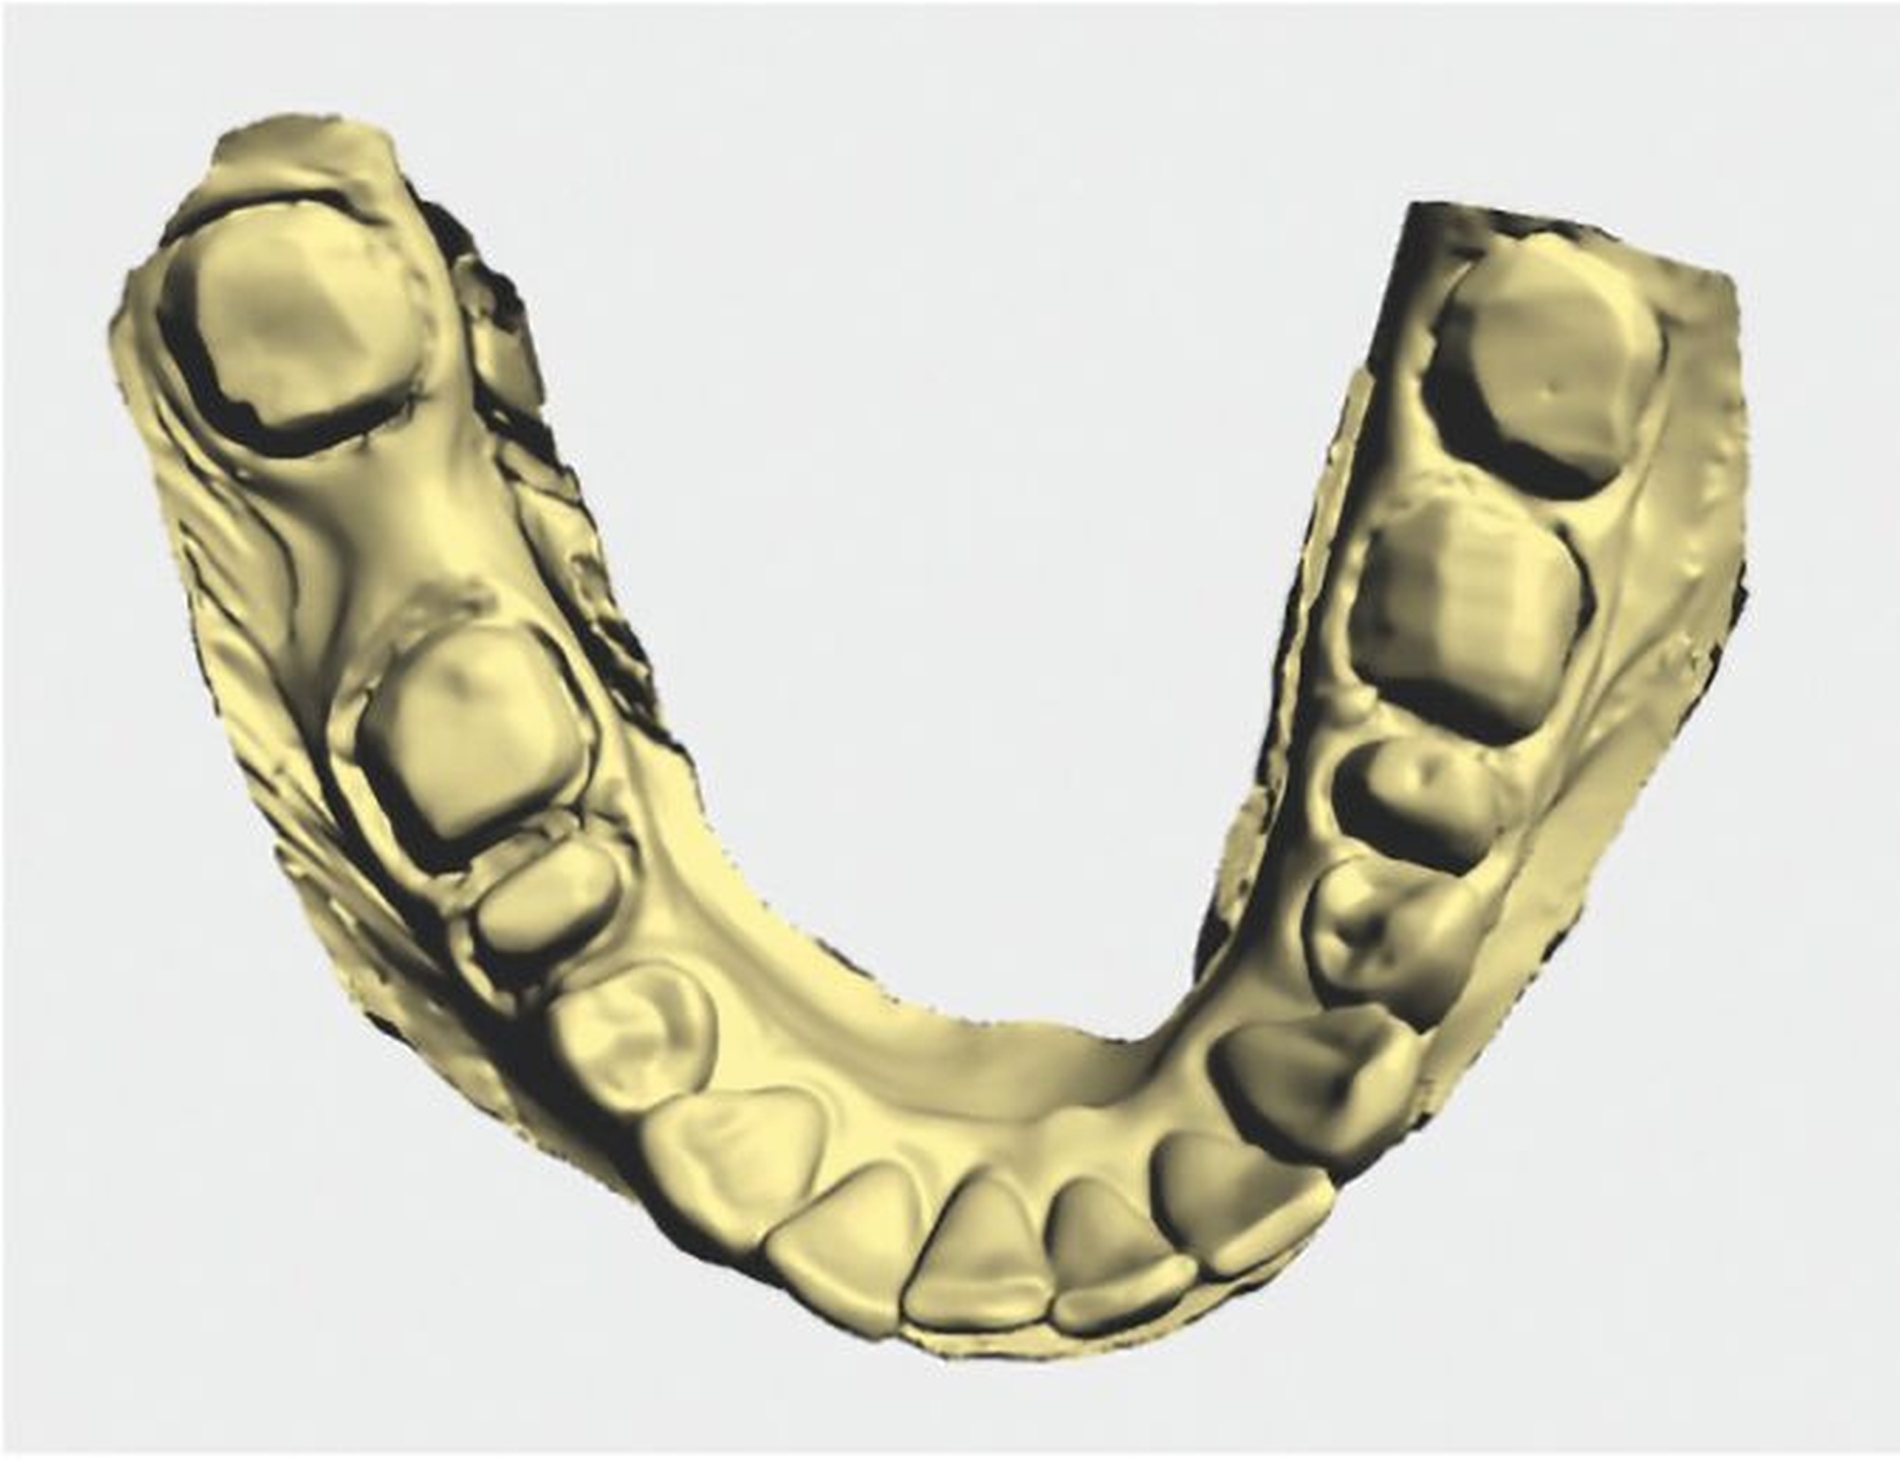

Nach Befürwortung des Therapiekonzepts durch einen Gutachter der gesetzlichen Krankenkassen wurden alle alten insuffizienten Amalgamfüllungen durch Aufbaufüllungen aus Komposit ausgetauscht. Nach Präparation der entsprechenden Zähne (Abbildungen 7a bis 7c), wurden diese mittels Doppel-Fadentechnik auf den Intraoralscan (Abbildung 7d) mittels Primescan™ (Dentsply Sirona) vorbereitet.

Da die Stützzonen in diesem Fall komplett aufgelöst wurden, erfolgte das Scannen des Bisses über das sequenzielle Einsetzen der Provisorien, die auf Grundlage der neu definierten Kieferrelation hergestellt wurden. Die Provisorien dienten somit nicht nur dem Erhalt von Kaufunktion, Ästhetik und Phonetik, sondern kamen auch beim Scannen als eine Art Bissschablone zum Einsatz. Dies basiert grundsätzlich auf einer in der Literatur weitverbreiteten Methodik („prophylaktische Bissnahme“), bei der Bissschablonen aus dem Autopolymerisat Pattern Resin vor der Präparation und der Auflösung der Stützzonen angefertigt wurden [Jude et al., 1977].

Der festsitzende Zahnersatz wurde im zahntechnischen Labor designt und aufgrund der hohen Zahl der abzuformenden Zähne zunächst aus dem PMMA Telio® CAD (Ivoclar Vivadent) gefräst, um das suffiziente Abschließen der Kronenränder sowie die statische und dynamische Okklusion überprüfen zu können (Abbildungen 8a bis 8c). Danach folgte die Rohbrandanprobe (Abbildung 9). Hierbei konnten noch einmal final Form und Farbe überprüft werden, bevor die Kronen mit einem Glanzbrand schließlich ihre endgültige Gestalt (Abbildung 10) annahmen. Im letzten Schritt wurden die Kronen schließlich mit RelyX™ Unicem 2 (3M™) selbstadhäsiv auf den Stümpfen befestigt. Mit dem Endergebnis war die Patientin hochzufrieden.